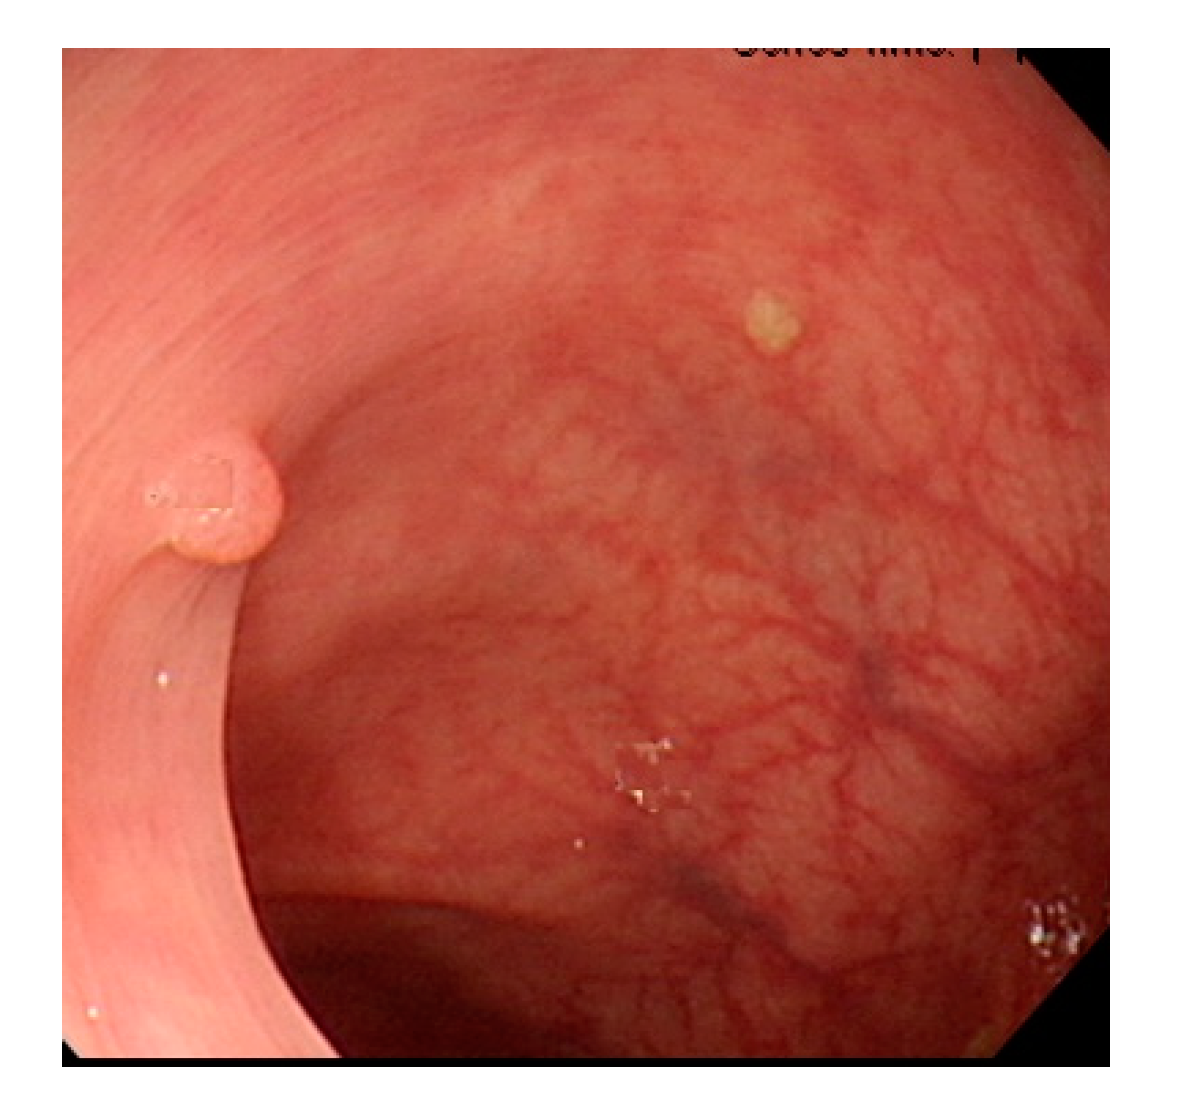

Currently, common magnifying NBI diagnostic classifications are the Sano, Hiroshima, Showa, and Japan narrow-band imaging expert team (JNET) classifications, and the most prevalent non-magnifying NBI diagnostic classification is the NBI international colorectal endoscopic (NICE) classification (Table 1 and Figure 1) [8,9]. In most of these classifications, the histopathology of polyps is determined based on the optical characteristics of lesion color, structure of capillaries, and morphology of capillary surface. The NICE classification, for instance, categorizes colorectal polyps as type 1, hyperplastic polyps; type 2, adenomas, intramucosal carcinoma, or superficial submucosal carcinoma; and type 3, deep submucosal carcinoma. Rectosigmoid diminutive (≤5 mm) hyperplastic polyps are considered as non-neoplastic polyps without malignant potential [8]. The recently developed Workgroup serrAted polypS and Polyposis classification can enhance the diagnostic accuracy of sessile serrated adenoma polyps [10].

Figure 1.

Example image of NICE classification.